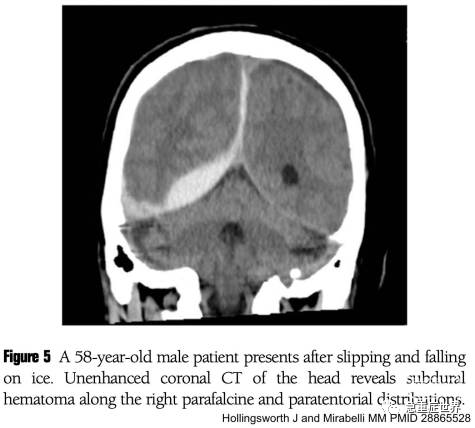

硬脑膜下血肿在影像上呈新月形,通常包在颅骨上。

硬膜下血肿可以穿过颅骨缝。血液可能会沿着大脑镰和/或小脑幕延伸(下图)。